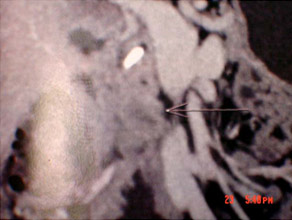

CT scan of Chronic pancreatitis with cancer (stent seen in the pancreatic duct, arrow pointing the tumor)

CT scan of chronic pancreatitis with large tumor, stones in the pancreatic duct